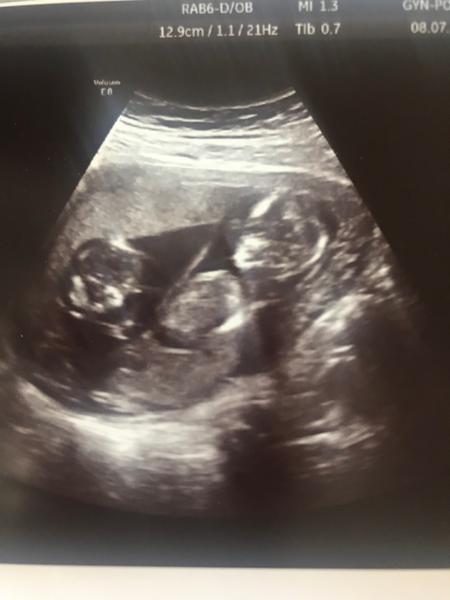

Tak na našem skreeningu ve 13tt nám paní dr. sdělila, že čekáme na 80% holčičku....radostně jsme sdělovali po rodině , že to bude holka, naštěstí jsem dala na svou intuici a nic nenakupovala, neb ve 20tt hned první věta paní doktorky byla to je kluk, jako buk 😕 😀 . A myslím si, že je to skutečně kluk, neb minulý týden byl chlapeček opět potvrzen a máme vyfocený jasný důkaz. Takže u nás se pohlaví ze 13tt nepotvrdilo a přitom mám štěstí a chodím také k výborné specialistce a na moderní UTZ.

🙂 nám řekli pohlaví při prvotrimestrálním screeningu ve 14tt - ale bylo to ve fakultní nemocnici na nejmodernějším UTZ. Od 11tt je prý zřetelný nějaký genitální výrůstek, takže ,,pindíka" mají ze začátku i holčičky, ale je u nich prý takový ochablý a upadne, proto se to ze začátku hodně plete. Dostali jsme video a ten náš mrňous má pořádnýho, tak snad neupadne 😀 No ikdyby, tak žádná trága 😉

To jsem teda neslysela, ze maji i holcicky ze zacatku vyrustek, ktery muze upadnout 😀 ale prave jsem hodne cetla, ze je takhle opravdu jeste brzy se stoprocentne spolehnout na pohlavi. I kdyz ja jsem na tom UTZ toho pindika taky videla 🙂 tak uvidime na dalsim UTZ jsem na to fakt zvadava, i kdyz nam rekli, ze to vypada na kluka, tak ji stejne porad myslim, ze to bude holcicka... 😉